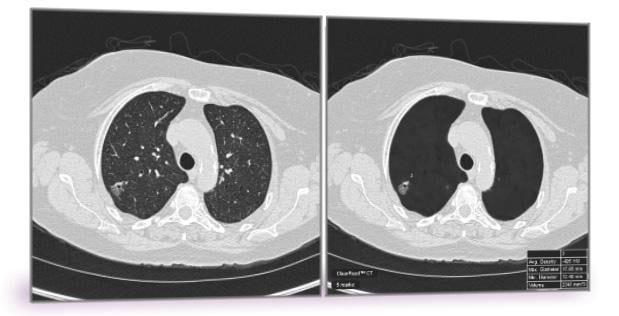

Riverain has been issued U.S. Patent 9,990,743 for its methodology to selectively remove anatomical structures from CT scans to optimize reading accuracy and efficiency for lung cancer detection. The technology is used in the company’s premier software, ClearRead CT. Riverain said ClearRead CT is proven to lead to more accurate and efficient detection of lung nodules, the early indicator of lung cancer. A range of possible applications exists within other imaging modalities including magnetic resonance imaging (MRI), positron emission tomography (PET), full field digital mammography (FFDM) and tomosynthesis, where normal structures interfere with the detection and diagnosis of disease.